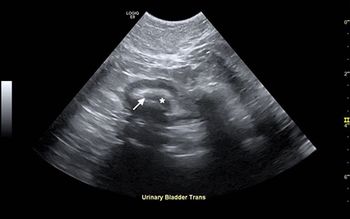

Examine the ultrasonograms, study the exam findings, and see if you can name the cause in this feline patient with hematuria and recurrent UTIs.